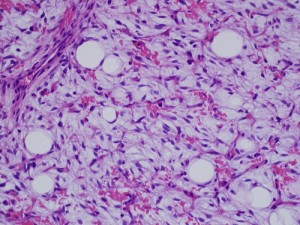

Gross image (far left image) shows a multinodular reddish and pinkish fatty mass, while the low-power and high-power microscopic images (middle and far right images) reveal a mucoid matrix with lipoblasts at different maturational stages (spindle-shaped mesenchymal cells to univacuolated cells with compressed nuclei).

Pathologic diagnosis: Lipoblastomatosis.

On gross pathology, lipoblastomas may be red, pink, white, tan, light yellow or yellowish-grey and frequently measure less than 5 cm and are well-encapsulated, while lipoblastomatosis, being infiltrative, tends to be larger and less defined, a point illustrated by this patient. At histology, they show univacuolated or multivacuolated lipoblasts, myxoid stroma, spindled-to- stellate mesenchymal cells, a plexiform capillary network, and mature lipocytes. Ultrastructurally, they consist of cells ranging from perilipoblasts (spindle cells) to mature adipocytes.